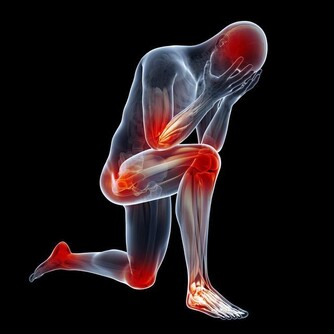

許多上班族工作一忙起來,連上廁所的時間都沒有,強忍著尿意,長期下來對健康恐造成一大傷害!

台北市立聯合醫院仁愛院區泌尿外科黃建榮醫師提醒,憋尿會讓毒素一直留在體內,

長期下來不僅會讓膀胱無力,且容易造成細菌感染、發炎,

甚至導致腎臟永久性的傷害,宜小心留意避免憾事發生。

長期憋尿健康的影響有哪些呢?

1. 尿道感染:正常排尿時可以將尿道口的細菌沖走,

若長時間憋尿,大量細菌累積在尿道,就容易引發感染問題。

2. 膀胱發炎:憋尿會使膀胱脹大、膀胱粘膜缺血,當遇上自身抵抗力不足時就容易出現急性膀胱炎。

當發生急性膀胱炎時,膀胱壁敏感,一有尿液就會想上廁所,造成就頻頻跑廁所又只能解出一點尿,

甚至連帶出現解尿有灼熱感或血尿等。

3. 膀胱損傷:長期憋尿恐使膀胱脹大,膀胱壁肌肉變薄,影響膀胱收縮彈性,

而產生頻尿、尿不乾淨、甚至會有尿不出來的感覺。

4. 前列腺炎與副睪丸炎:男性若排尿次數太少,可能使細菌透過尿道引發感染,造成前列腺炎或副睾丸炎問題。

5. 尿毒症:憋尿也可能使得尿液回流到腎臟,造成腎積水引起尿毒症等嚴重後果,恐造成腎臟永久性的傷害。